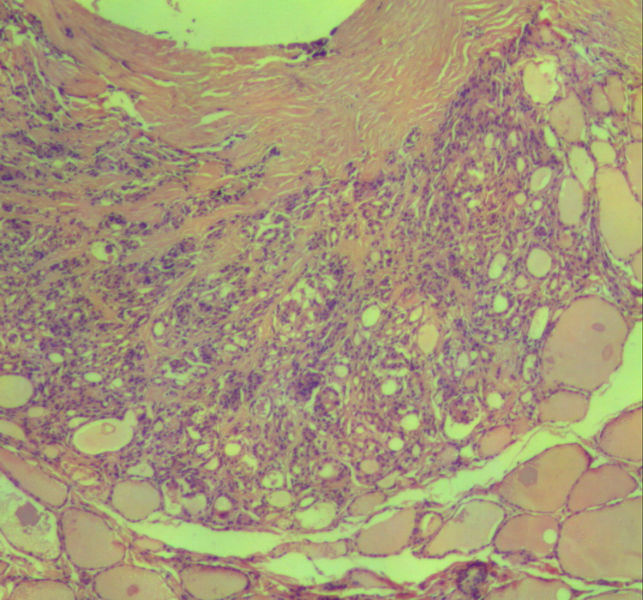

女,45岁,体检发现颈前区一结节,术中送检甲状腺左腺叶,发现一界清结小1*0.8cm,灰黄色。术中诊断滤泡性肿瘤伴包膜累及,局部疑包膜穿破,滤泡癌可能,待石蜡报告。石蜡连续切片形态见图,可见明显包膜穿破,诊断为滤泡性癌。患者借片到上级医院会诊,结果为:包膜内滤泡癌伴包膜累及。请问有包膜内滤泡癌的提法吗?这个病例怎么诊断啊?请各位老师多指导。

• 这个是滤泡性癌吗图1

图1